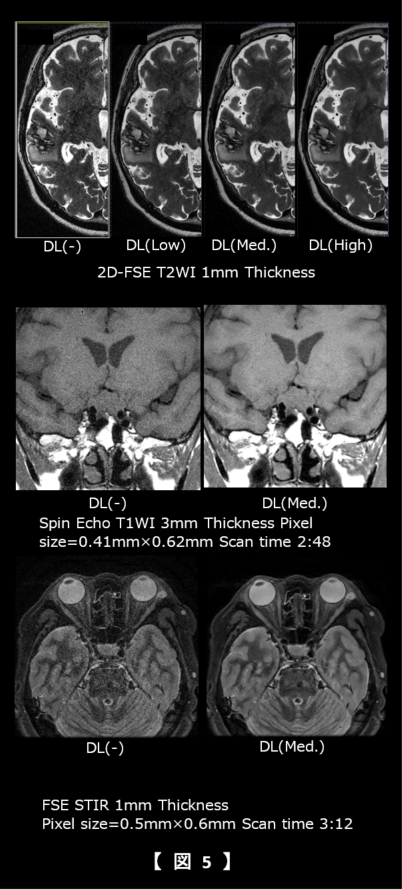

その結果、スライス厚が薄くなる(ボクセルサイズが小さくなる)につれSNR上昇率が上昇した(図3)。十分なSNRがある10mmでは10%程度であるの対して5mmで40%、1mmまで薄くなると100%のSNRの上昇率を認めた。AIR™ Recon DLには、「Low」「Medium」「High」の3段階の設定が可能である。それぞれについて93-402S型ファントムのピンパターンとスリットを使用して尖鋭性について視覚評価を行った。ピクセルサイズは0.32mmである。その結果、いずれのレベルにおいても0.5mmのピンパターンは評価可能になり、「High」がもっとも視認性が優れていた(図4)。

頭部領域では、脳や眼窩領域の従来より薄いスライス厚を臨床上現実的な撮像時間で、下垂体領域では従来より高SNRで収集することが可能となり(図5)、整形領域ではオフセンターの高SNR・高分解能画像に加え、低SNRのDWIにおいてもSNRを向上させることで診断能の向上に寄与していると考えられる(図6中段)。また腹部の膵管領域においても高空間分解能に撮像することが可能となった。さらにBWを広帯域化することでケミカルシフトの低減と高空間分解能かつ高SNR画像の両立が期待できる(図6下段)。